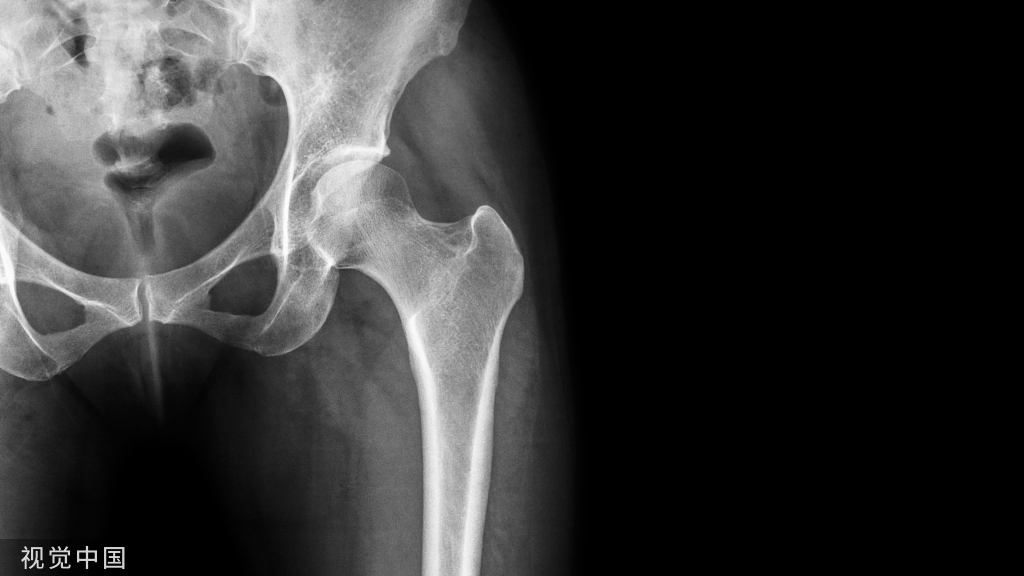

其他辅助检查:X 线照片显示肿物的软组织当中有分散钙化影。过一段时间,急性期的症状和体征消失后,肿物变小,钙化影也缩小,但密度增高。X 线片上可见柱状或不规则形态的团块状不同密度的骨化阴影,可与骨骼相连,也可完全游离。骨骼呈现失用性萎缩。

(FOP患者的X光片,异位骨化影响整个骨骼系统的形态,除局部的变形之外,脊柱也无法伸直)